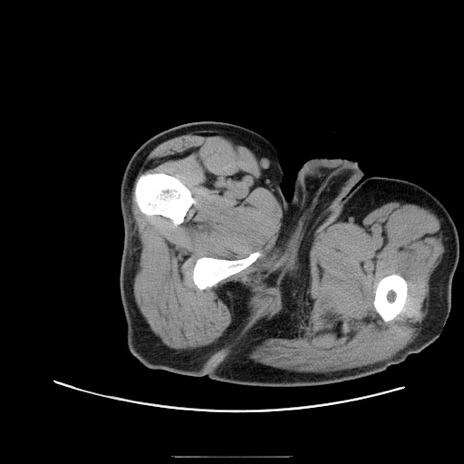

冠状断像

【症例】50歳代男性

【主訴】腹痛

【現病歴】AVMからの被殻出血のため回復期リハ病棟入院中。 本日午後3時頃急に下腹部痛が出現した。

【既往歴】AVM、被殻出血、虫垂炎、高血圧

【身体所見】意識晴明、左半身不全麻痺、会話の理解は良好、36.5°C、腹部:膨隆、全体に板状硬、下腹部正中に圧痛点あり、反跳痛-、筋性防御不明、右下腹部にope scar

【データ】WBC 9400、CRP 0.06